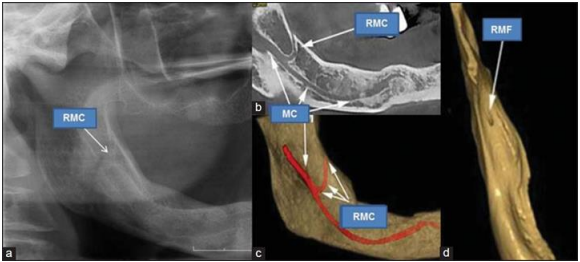

Prevalence, dimension and location of retromolar canal on cone beam computed tomography: An Analytical cross sectional study

Prevalence, dimension and location of retromolar canal on cone beam